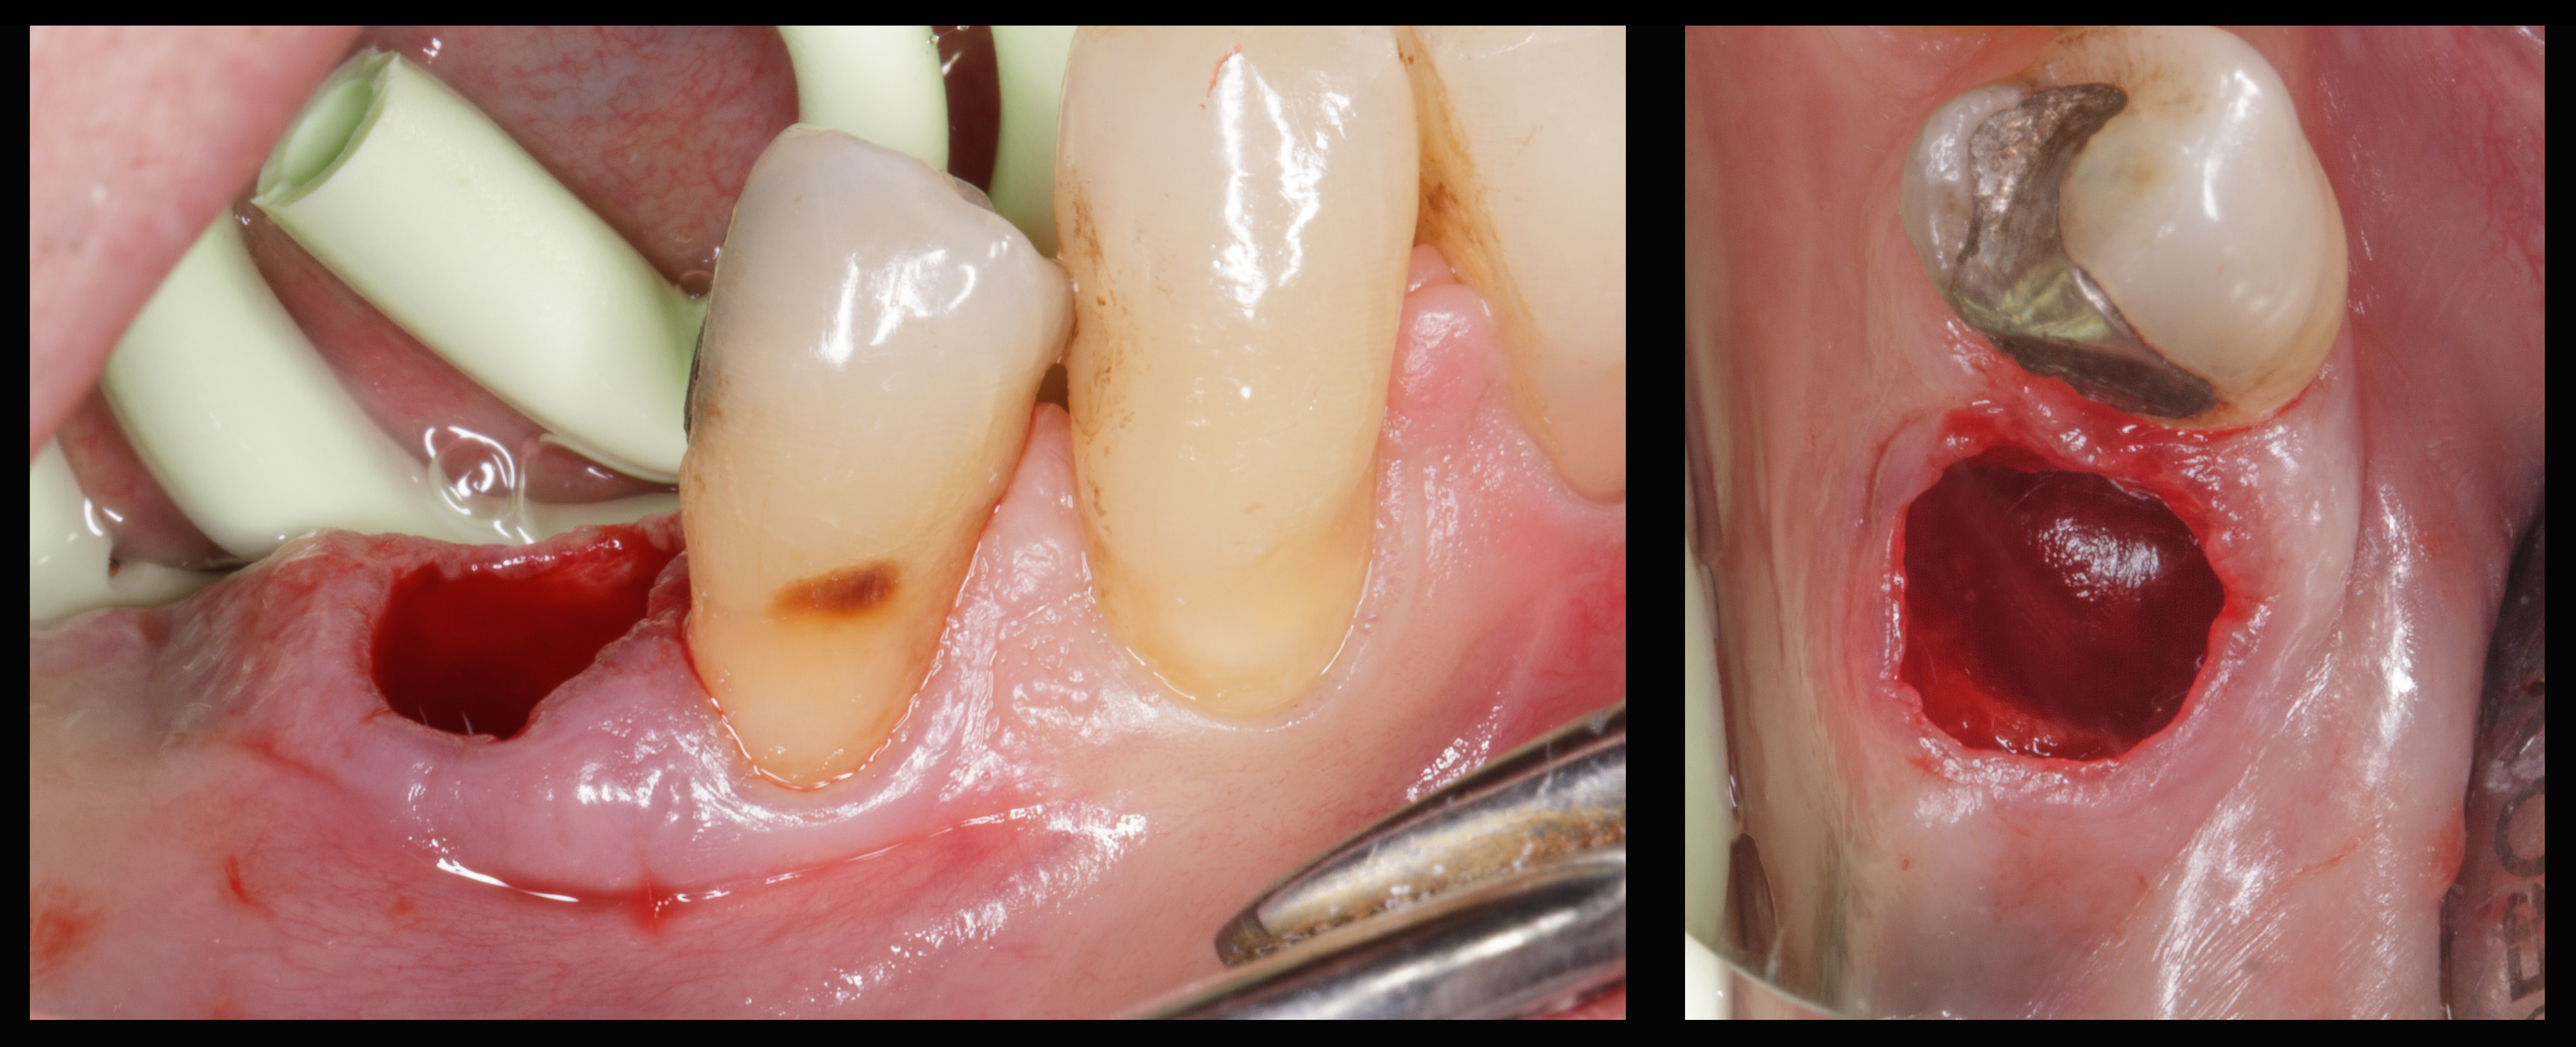

Si procede pertanto all’estrazione della radice senza esecuzione di lembo muco-periosteo e nel modo più atraumatico possibile.

Dopo l’estrazione dentaria si procede a debridement completo dell’alveolo dal tessuto infiammatorio, eseguito solo con strumenti manuali, courettage del margine gengivale con fresa diamantata per rimuovere lo strato epiteliale interno e garantire un maggiore apporto di sangue all’innesto (Figura 7).

Si effettua un bone mapping con la sonda parodontale per valutare la perdita di sostanza ossea della parete vestibolare. L’entità del difetto osseo è di circa 8 mm in senso corono-apicale per 5 mm in senso mesio-distale.

In caso di frattura radicolare verticale è frequente il riscontro di deficit osseo della parete alveolare vestibolare causato dal biofilm batterico presente nella discontinuità radicolare.

Il protocollo chirurgico nella ridge preservation con una parete ossea non integra prevede l’inserimento di una membrana riassorbibile in collagene (NeoGen® Flex) all’interno dell’alveolo in maniera che faccia da barriera per le cellule epiteliali a mitosi veloce e nello stesso tempo impedisca la dislocazione vestibolare del particolato osseo eterologo innestato nell’ alveolo (Figura 8).